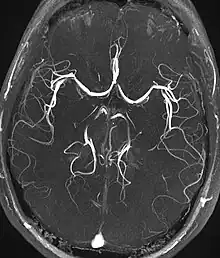

Angiography

Magnetic resonance angiography

Magnetic resonance angiography (MRA) generates pictures of the arteries to evaluate them for stenosis (abnormal narrowing) or aneurysms (vessel wall dilatations, at risk of rupture). MRA is often used to evaluate the arteries of the neck and brain, the thoracic and abdominal aorta, the renal arteries, and the legs (called a "run-off"). A variety of techniques can be used to generate the pictures, such as administration of a paramagnetic contrast agent (gadolinium) or using a technique known as "flow-related enhancement" (e.g., 2D and 3D time-of-flight sequences), where most of the signal on an image is due to blood that recently moved into that plane (see also FLASH MRI).[51]

Techniques involving phase accumulation (known as phase contrast angiography) can also be used to generate flow velocity maps easily and accurately. Magnetic resonance venography (MRV) is a similar procedure that is used to image veins. In this method, the tissue is now excited inferiorly, while the signal is gathered in the plane immediately superior to the excitation plane—thus imaging the venous blood that recently moved from the excited plane.[52]